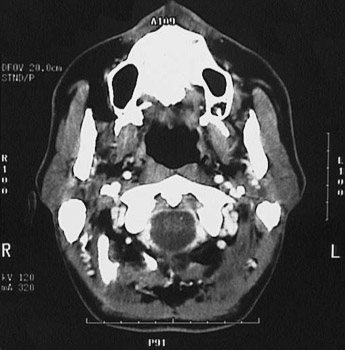

This is a normal axial head and neck CT scan demonstrating the maxilla and nasopharynx and maxillary sinus and ramus of mandible and masseter muscle and foramen magnum and mastoid process and C1 and vertebral artery and internal jugular vein and internal carotid artery and parotid gland.